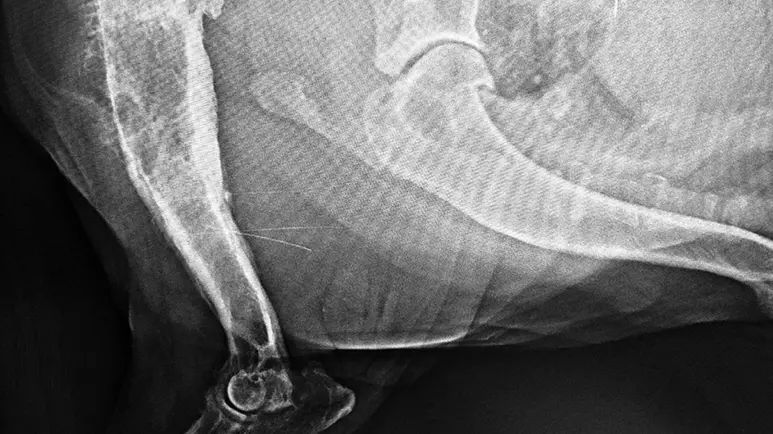

The primary diagnostic tests for osteosarcoma are X-rays and histopathology (examination of tissue). On an X-ray, osteosarcoma has a characteristic lytic or “moth-eaten” appearance. A fine-needle aspirate or bone biopsy of suspicious areas must be performed to confirm the diagnosis.